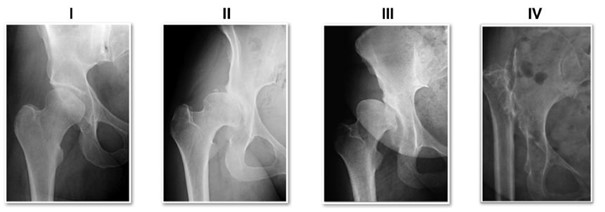

Crowe et al [7], based on their understanding that the degree of difficulty of THAs is associated with the severity of the dislocation and the subsequent distortion of normal bone and soft-tissue anatomy, grouped the dysplastic hips into four types based on the amount of dislocation (subluxation): < 50% in type I, 50–75% in type II, 75–100% in type III, and more than 100% in type IV.

As shown in Figure 1, the amount of deformity in DDH can progress from mild subluxation with a shallow socket (type I) to high dislocation of the hip joint accompanied by an absence of the femoral head and neck and a deformed pelvis (type IV). While a THA in DDH where subluxation is less than 50% has "no greater technical difficulty at surgery than a hip with severe osteoarthritis" [7], THAs in highly deformed DDHs are challenging and require special skills and consideration [2, 7].